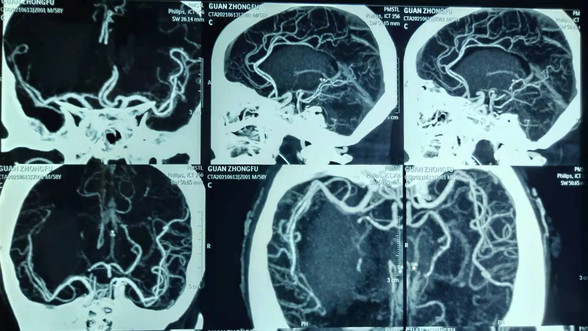

术中导航影像

手术由高风全副主任医师和王云龙副主任医师共同完成,在神经外科机器人引导下,定位数据从术前CT上获得,以此作为定位依据确定穿刺点和靶点完成手术设计,精准打靶,成功完成立体定向下脑出血精准穿刺引流手术,术后当日患者即恢复自主意识。